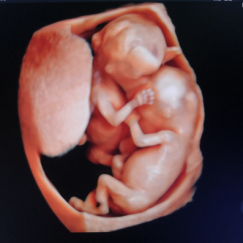

产科四维超声检查